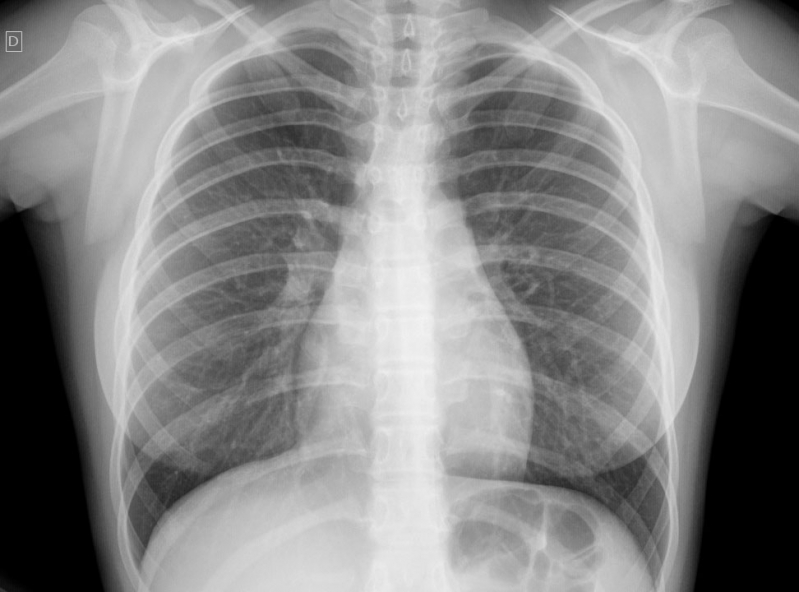

Impressora para Raio-x

RS IMPRESSORASUma impressora para raio-x deve ser específica para que haja o perfeito resultado, principalmente, se houver algum incoveniente que necessita de tratamento. Esse tipo de equipamento é...

Uma impressora para raio-x deve ser específica para que haja o perfeito resultado, principalmente, se houver algum incoveniente que necessita de tratamento. Esse tipo de equipamento é imprescindível em hospitais e clínicas.

Para uma peça de excelência, é de extrema autoridade contar com a ajuda de profissionais especializados e aptos a expandir um serviço de particularidade.

Uma impressora para raio-x deve ser específica para que haja o perfeito resultado, principalmente, se houver algum obstáculo que necessita de tratamento. Esse tipo de equipamento é imprescindível em hospitais e clínicas.

Para uma peça de excelência, é de extrema seriedade contar com a ajuda de profissionais especializados e aptos a ampliar um serviço de particularidade.

Impressora para Raio-x

Impressora para Raio-x

Impressora para Raio-x

RS IMPRESSORASUma impressora para raio-x deve ser específica para que haja o perfeito resultado, principalmente, se houver algum obstáculo que necessita de... Cotar Agora Saiba Mais

Impressora para Raio-x

Impressora para Raio-x

Impressora para Raio-x

RS IMPRESSORASUma impressora para raio-x deve ser específica para que haja o perfeito resultado, principalmente, se houver algum incoveniente que necessita de... Cotar Agora Saiba Mais